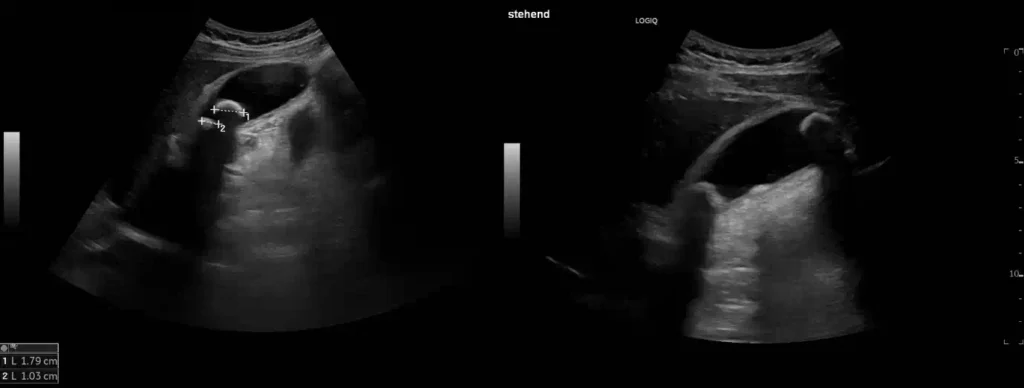

Längsschnitt über der Gallenblase

Leberabszeß

Im Längsschnitt über die Gallenblase erkennt man anstelle eines glatt begrenzen Gallenblasenlumens eine unregelmäßig begrenzte echoarme Flüssigkeitsansammlung im Gallenblasenbett und ventral der Leber. Es handelt sich hier um eine perforierte akute Cholecystitis auf Basis einer Cholecystolithiasis, welche bereits nach einer kurzen Schmerzperiode von 48h eingetreten ist. Eine solche Komplikation kann durch eine rasche Sonographie und anschließende chirurgische Vorstellung vermieden werden.